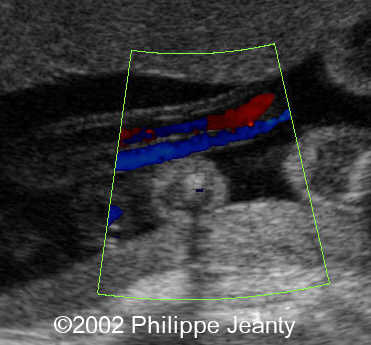

Ultrasound appearance

A transverse section of the umbilical cord shows two vessels. Examination of umbilical blood flow with color Doppler may facilitate diagnosis. However, by far the easiest way to assess the number of arteries, is by identifying the intra-abdominal portion of the umbilical artery along side the bladder with color Doppler17,18.